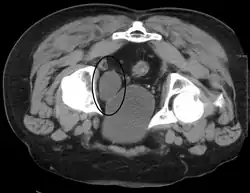

Calcifications on bladder wall caused by urinary schistosomiasis

Cystitis refers to infection or inflammation of the bladder. It commonly occurs as part of a urinary tract infection.[25] In adults, it is more common in women than men, owing to a shorter urethra. It is common in males during childhood, and in older men where an enlarged prostate may cause urinary retention.[25] Other risk factors include other causes of blockage or narrowing, such as prostate cancer or the presence of vesico-ureteric reflux; the presence of outside structures in the urinary tract, such as urinary catheters; and neurologic problems that make passing urine difficult.[25] Infections that involve the bladder can cause pain in the lower abdomen (above the pubic symphysis, so called "suprapubic" pain), particularly before and after passing urine, and a desire to pass urine frequently and with little warning (urinary urgency).[25] Infections are usually due to bacteria, of which the most common is E coli.[25]